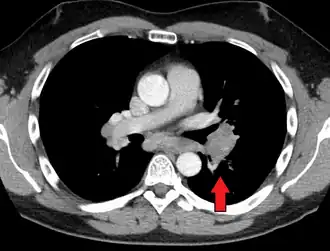

Hilar adenopathy especially on the person's left (coronal CT) -

Hilar adenopathy especially on the person's left (transverse CT)